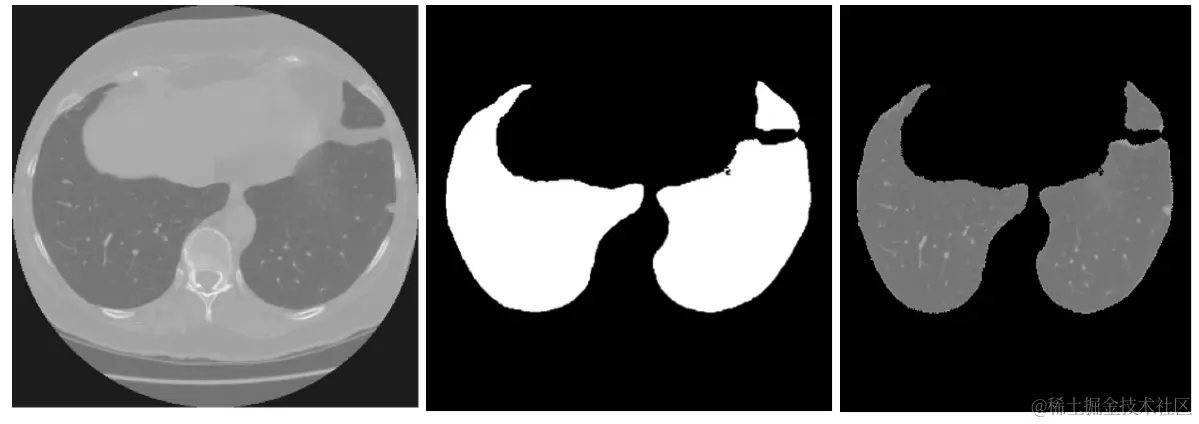

三、数据预处理—肺部区域提取

根据以往比赛的经验,肺结节检测需要先把肺部区域提取出来。我们的实战经验发现,这一点很重要。提取肺部区域的好处也很明显:主要体现在减少了无关区域对model的影响,使model在更小的区域规模进行预测。

由于之前有类似比赛,我们综合了前面比赛的一些经验,实现了我们的肺部区域提取代码。大致的流程如下:

1. 根据图形学信息进行label标注,使相邻区域有相同的label。这一过程需要注意,由于实际影像没有严格的区域的划分,导致存在一些很小的区域,这些小区域包含在更大的区域里面,单从label层面讲,他们属于小区域,但它们真正的label其实是和大区域一致的。具体的实现就是参考周围区域的label,进行区域label扩散。可参考scipy.ndimage.binary_dilation函数

2. 提取面积最大的两个label区域,这两个区域就是两个肺结节